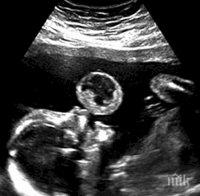

Столична болница спешно търси кръводарители за все още неродено бебе, съобщи Нова телевизия.

От МБАЛ „Надежда" призовават всички желаещи с кръвна група 0 (-) да дарят в четвъртък кръв в Националния център по хемотрансфузиология.

Дарителите трябва да заявят изрично, че кръвта им трябва да бъде пренасочена за нуждаещото се бебе в болницата.

„Нека да спасим живота на едно още неродено бебче, нуждаещо се спешно от вътреутробно кръвопреливане, без което няма да може да оцелее", призовават медиците. И подчертават, че разполагат „само с утрешния ден".